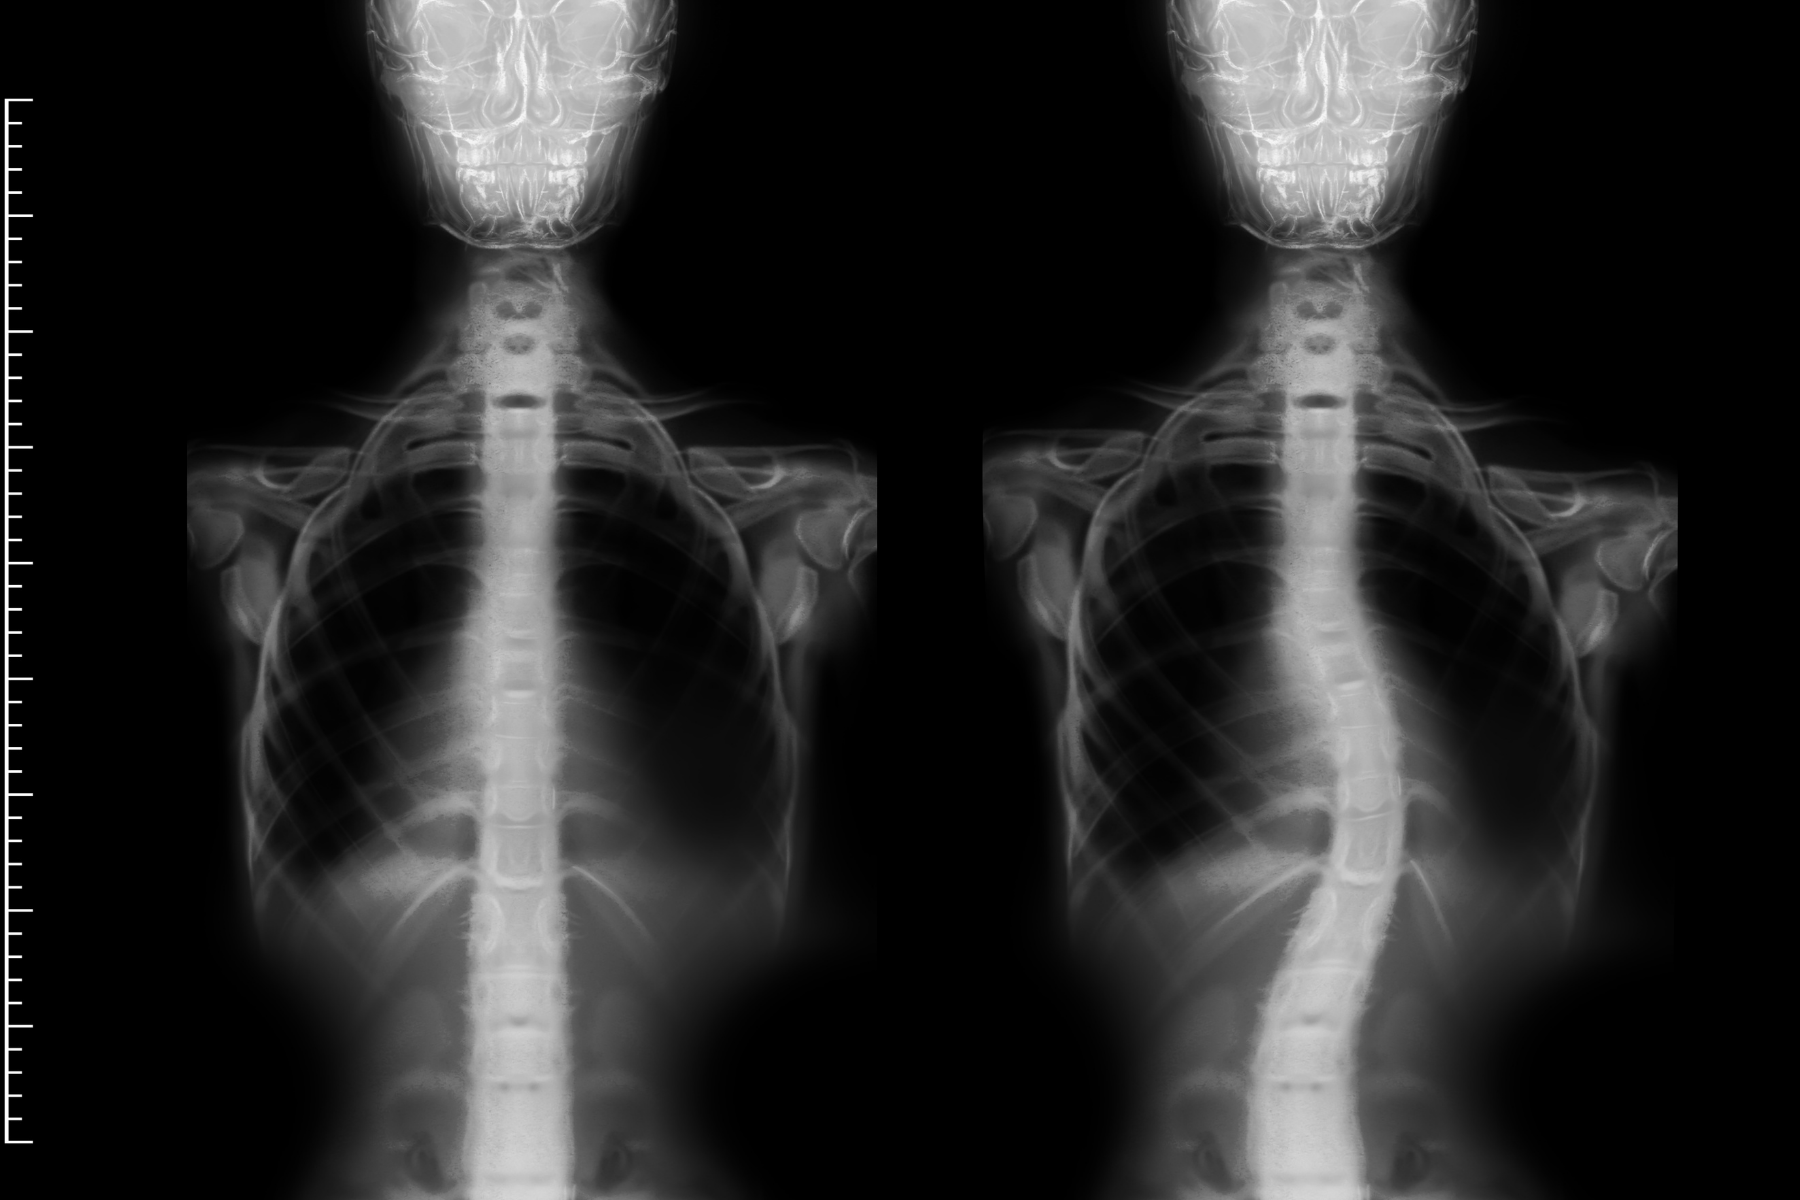

Every form of scoliosis involves an abnormal lateral curvature of the spine greater than

10 degrees, typically accompanied by vertebral rotation. That rotation, the three-

dimensional twisting of the spine, is what distinguishes scoliosis from simple postural

asymmetry and what makes it visible on a forward-bend test as a rib hump or flank

prominence.